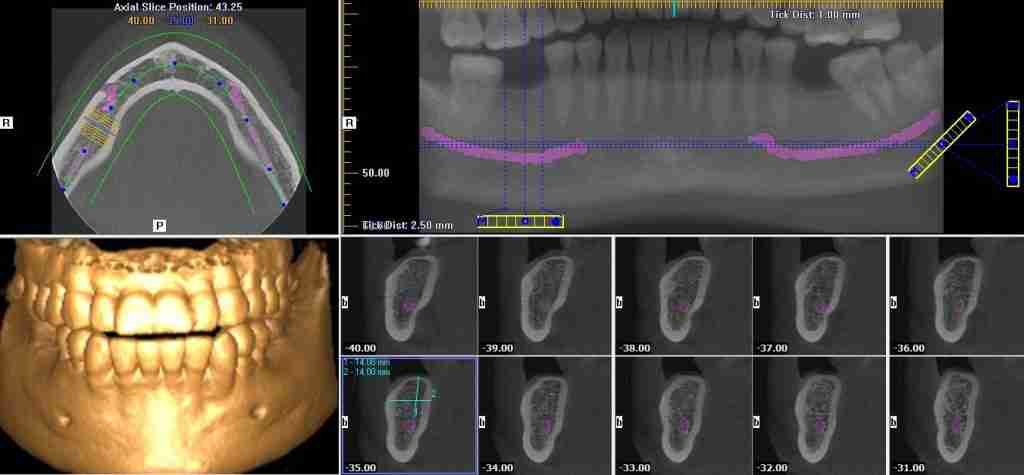

Advanced 3D Dental Scan for Precise Results

Experience 3D dental scans that are both precise and painless with ct-dent.co.uk. Count on our state-of-the-art technology to deliver precise results and ensure a pleasant experience.